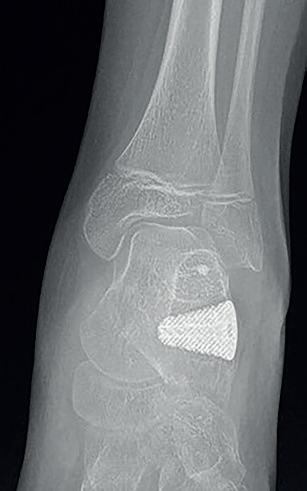

Obr. 6 RTG snímek pacienta po operaci dle Gricea s užitím 3D implantátu.Mezi kloubní výkony patří vytvoření kloubních zarážek, tzv. arthroereisis, a ztužení kloubů, arthrodesis. V léčbě plochonoží se často provádějí subtalární extraartikulární arthroereizy, při kterých je vytvořena kloubní zarážka v oblasti sinus tarsii k omezení nadměrného pohybu subtalárního kloubu a ke znovuobnovení mediální klenby nohy, příkladem může být operace dle Gricea–Greena.25,26 Jako zarážka může být použit autologní kostní štěp či implantát. Použití implantátu s sebou nese snížení operační zátěže kladené na pacienta a zkrácení délky operace, neboť odpadá nutnost odběru kostního štěpu. Na trhu existuje široké spektrum používaných implantátů, které mohou být vyrobeny z nevstřebatelného i vstřebatelného materiálu.27,28 Je možné využít i individuálně připravené implantáty a speciálně zhotovené instrumentárium. Na našem pracovišti byla provedena tato operace také s využitím implantátu vytvořeného metodou 3D tisku, na jehož vývoji jsme se podíleli. Díky 3D tisku má implantát unikátní porózní strukturu umožňující lepší prorůstání okolní kosti (osteointegraci implantátu), čímž dochází ke snížení rizika uvolnění implantátu a jeho selhání (obr. 5, 6). Artrodézy se při léčbě plochonoží u dětí používají až jako poslední řešení po selhání ostatních léčebných modalit. Jako nejefektivnější způsob ztužení kloubu se jeví trojí artrodéza nohy (déza subtalárního, talonavikulárního a kalkaneokuboidního kloubu), s tímto výkonem je však vhodné počkat do ukončení kostního růstu.29